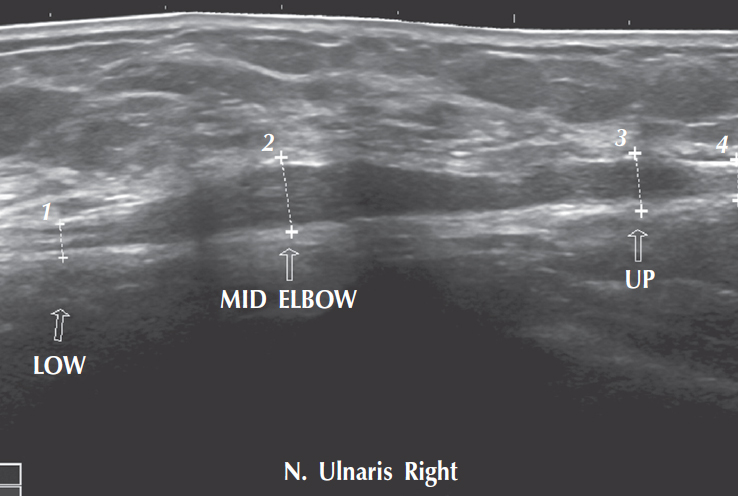

Кроме простоты использования, невысокой стоимости и доступности ультразвуковой метод диагностики имеет еще одно очень важное преимущество — возможность его использования по ходу операции. Так, при относительно небольших размерах опухоли и относительно плохой ее дифференцировке по ходу нерва возможно провести контактное УЗИ. Благодаря этому хирург получает возможность более четко определить границы опухоли по ходу нервного ствола. В практике интраоперационная УЗ-навигация использовалась неоднократно (рис. 2).

Рис. 2. УЗИ. Гипертрофия локтевого нерва на уровне кубитального канала

Fig. 2. Ultrasonography. Ulnar nerve hypertrophy at cubital tunnel level